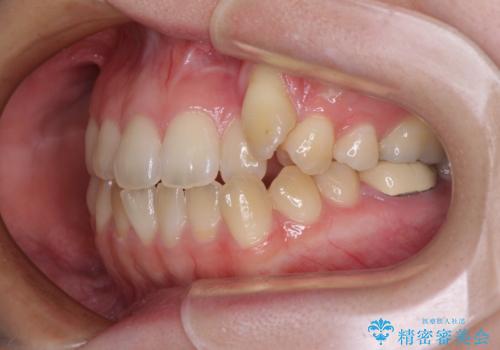

- 上顎の八重歯やデコボコを気にして来院された患者様です。

上顎歯列が狭窄していたため、急速拡大装置により上顎骨を側方に拡大しながら、ワイヤー装置にて矯正治療を行うこととしました。

上顎骨を拡大することで、八重歯やデコボコを歯列に収めることができ、下顎の歯が外に位置していた奥歯の咬み合わせも改善することができました。